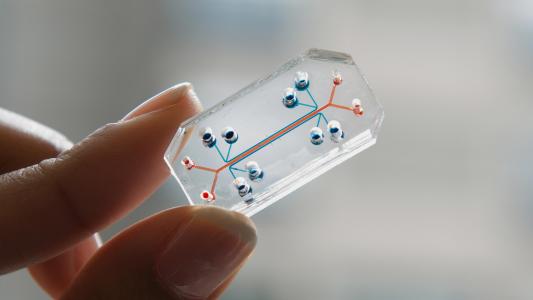

Human-like "organ chips" could eliminate animal studies

To rapidly test for COVID-19 treatments without animal studies, researchers make a model human body out of “organ chips.”